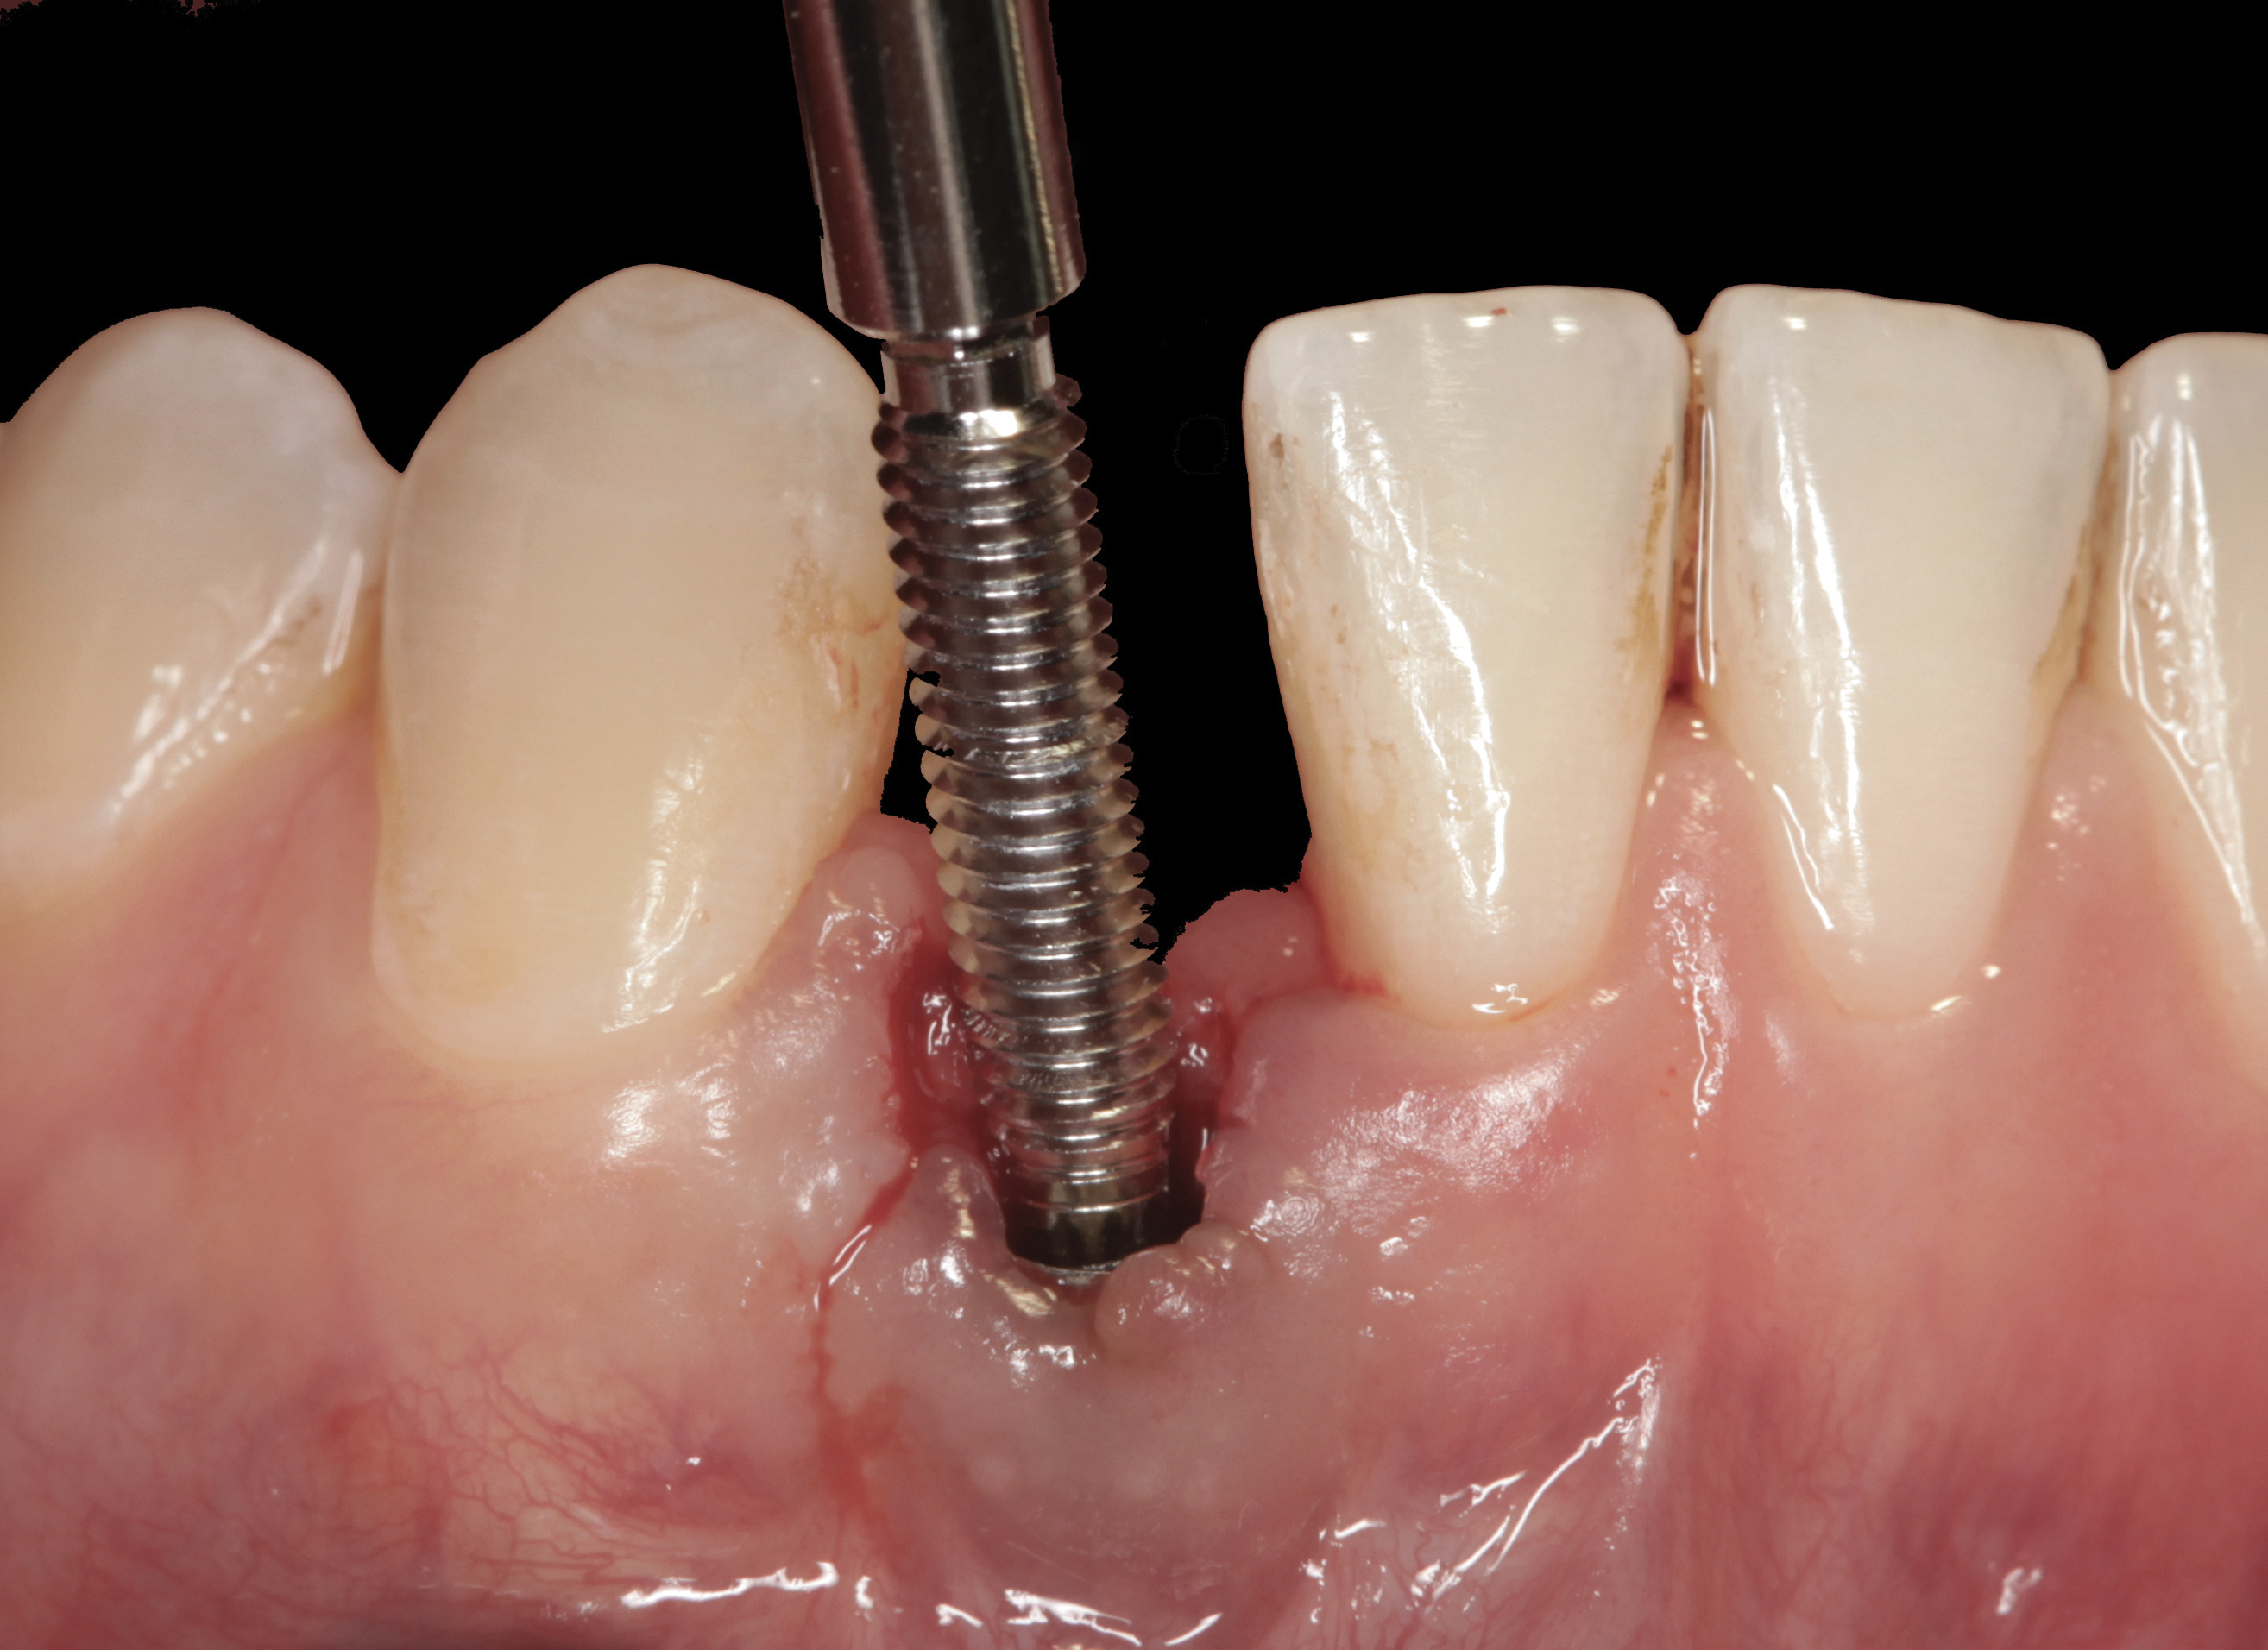

Fig 33. Excessive facial angulation of the implant placement shown with an abutment driver in the access screw hole.

Figure 33

Fig 34. A surgical cover screw was placed in an attempt to decoronate the implant and gain soft-tissue coverage in situ.

Figure 34

The following case report provides an example of this case scenario: A 24-year-old white male presented with congenitally missing tooth No. 26 restored with a single-tooth cement-retained implant restoration. The implant was placed excessively to the facial aspect of the edentulous site and too shallow, and the periodontal phenotype was thin scalloped (Figure 32). In an effort to mimic the lost midfacial soft tissues, pink ceramics were used as a cosmetic facade. Even though the restoration was not in the esthetic zone, the patient was highly displeased with the esthetic outcome and sought remediation.

The crown and screw-retained custom abutment were removed, and a surgical cover screw was placed into the implant, thereby allowing spontaneous gingival augmentation in situ (Figure 33 and Figure 34). Note that the lingual aspect of the implant site was significantly more coronal than the labial aspect, which was positive because the defect would be limited to a facial–lingual defect. A fixed RBR bridge was cemented on the adjacent teeth and used as a tooth-supported transitional provisional restoration (Figure 35). A few weeks were allotted to let the soft tissue heal and migrate around the cover screw (Figure 36) to see if there would be complete coverage, thereby allowing a soft-tissue augmentation procedure to be performed with primary flap closure as in clinical scenario No. 2. The major obstacle in achieving a positive tissue response was that the implant depth was also deficient because the implant–abutment connection was at the level of the free gingival margin. It was decided that the best treatment option would be to remove the implant. A high-powered reverse-torque device (Fixture Remover Kit, NeoBiotech, www.neobiotechus.com) was used to remove the implant atraumatically (Figure 38 through Figure 41). The implant socket was allowed to heal for several months not unlike an extracted tooth (Figure 42). A new implant was placed in a better position from both a restorative and esthetic perspective (Figure 43), and after a few months of healing, a new crown was made (Figure 44). A satisfactory functional and esthetic result was achieved (Figure 45 and Figure 46) without employing pink porcelain.